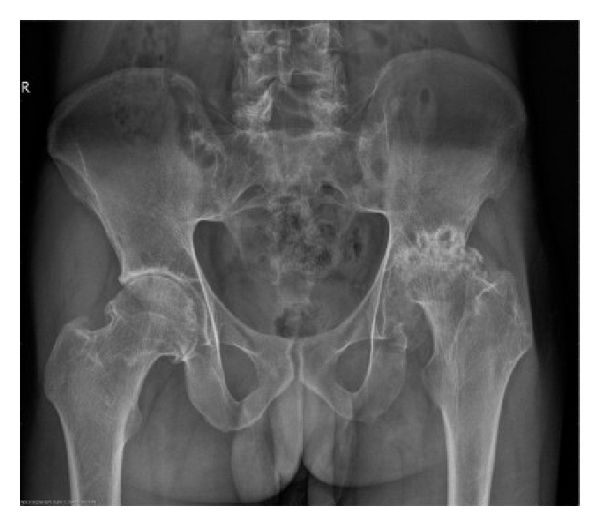

Preoperative characteristics of patients are listed in Table 1. The mean age and disease duration of patients were 37.1 ± 9.0 years (range: 24–52 years) and 13.7 ± 12.4 years (range: 2–40 years), respectively. HLA-B27 was positive in all patients. RF and ANA were negative. No patient had a history of iritis. Five patients had elevated ESR (5/7, 71.4%). Six patients had increased CRP (6/7, 85.7%). Radiographic evaluation of hips showed narrowed joint spaces ranging from 0 to 7 mm, including 3 of 7 patients with complete disappearance of the joint space (Figure 1). Serum levels of IgG and IgG4 were not measured.

(a)

(b)

(c)

(d)